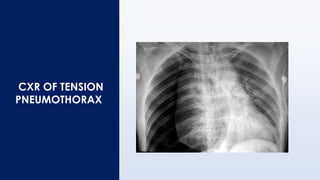

CXR OF TENSION

PNEUMOTHORAX

RADIOLOGICAL DIFFERENCES OF DIFFERENT CPM

No. Congenital lobar

emphysema

CCAM Tension Pneumothorax

1 Bronchovascular marking

present

Presence of septation in the

cystic lucent lesion with or

without air fluid level;

Vascular marking present

Absent

2 Compression of adjacent

lobes pushes the

diaphragm in cephalad or

caudal direction

Lack of lucency in the

uninvolved apical region

Lung collapses towards the

hilum

3 Management – lobectomy Excision of cyst Chest tube drainage

4 CT Scan – evaluates

anatomy of

emphysematous and its size

and relation

Can delineate exact size

and number of cystic

lesions

N/A